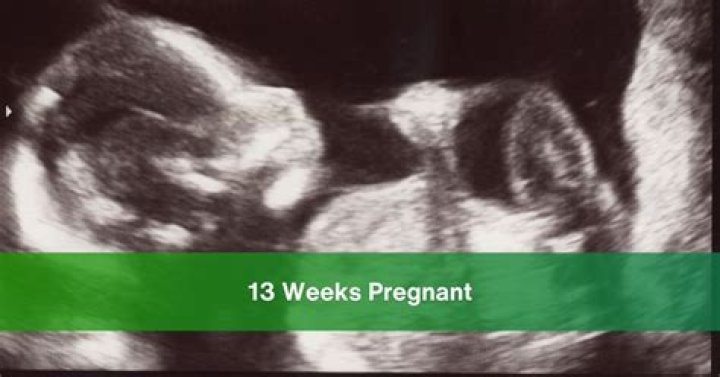

13 Weeks Pregnant Is How Many Months? At 13 weeks pregnant, you’re three months pregnant, although doctors track pregnancy by week, not month. This is the last week of the first trimester.

How many cm is a 13 week fetus?